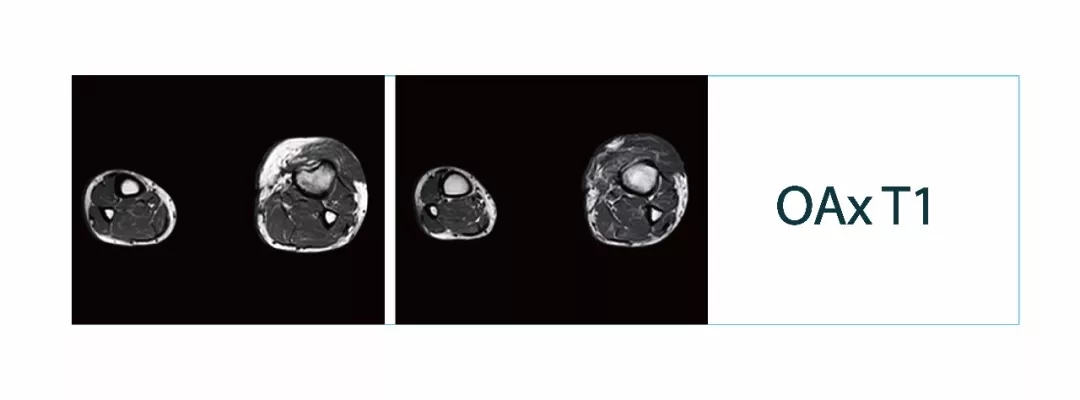

【朗润影像档案】磁共振影像病例分享(编号20180209)